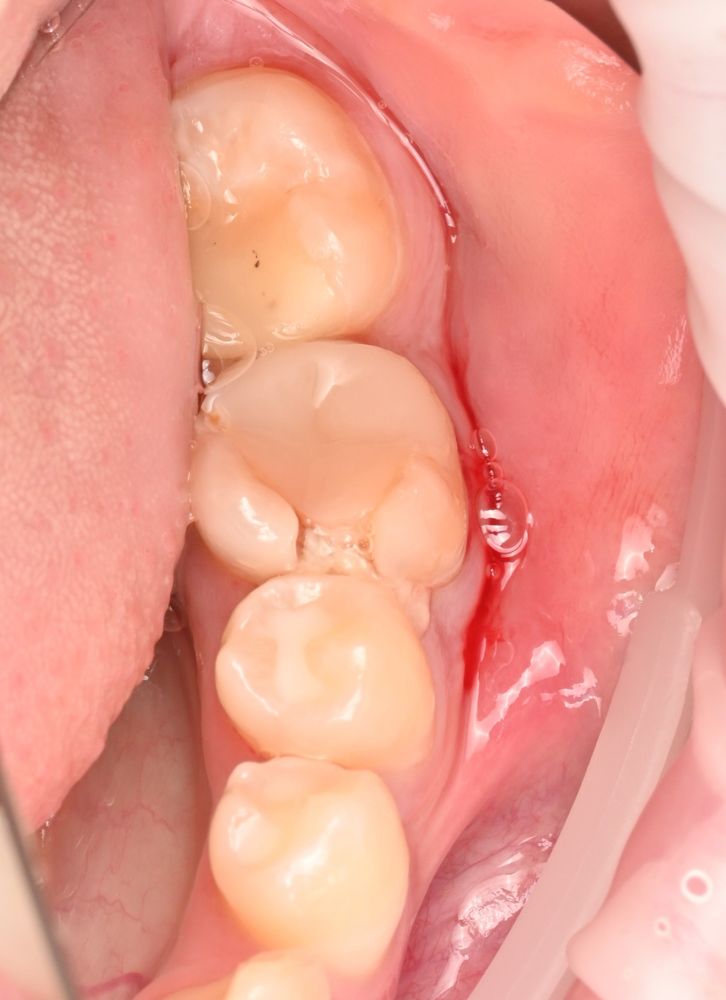

16-летний подросток обратился к нам с сильно разрушенным жевательным зубом.

До этого он уже лечил каналы, но воспаление вокруг корня продолжало расти.

Зуб 3.6 - коронка значительно разрушена, на КЛКТ видим, что каналы зуба раньше лечили, но все равно результат неудовлетворительный: имеется патологическая резорбция дистального корня и очаг инфекции вокруг корней.

Сохранить зуб было невозможно — его нужно было удалять.